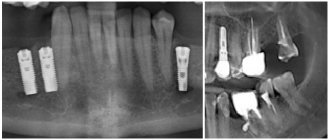

2. Различные проблемы с зубами, такие как кариес, воспаления десен, периодонтит, пульпит, остеомиелит и пр. Обычно они проявляются пульсирующей выраженной болью, которая усиливается при жевании твердой пищи или надавливании. Если же у пациента остеомиелит, то это также сопровождается отеком на лице, повышенной температурой и особо интенсивной болью.